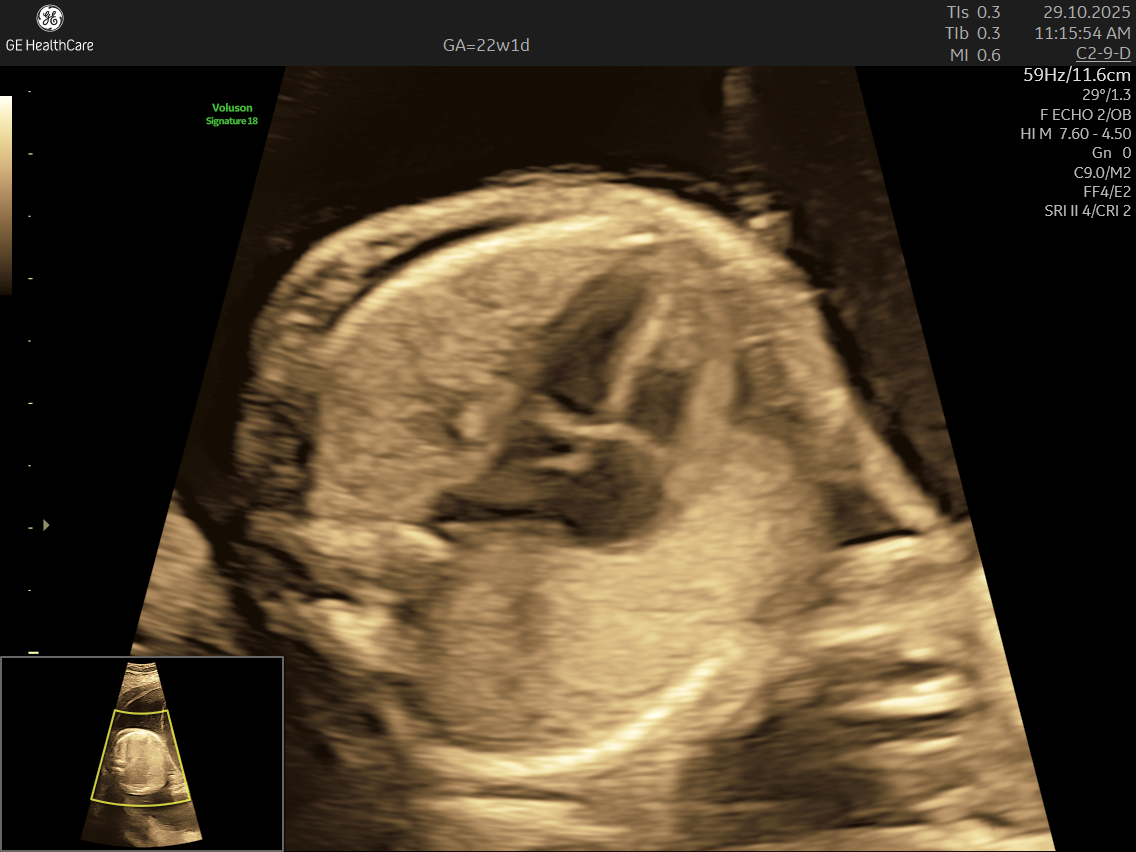

Fetal echocardiography is a valuabe early screening tool for Fetal Heart Defects. It is a specialized ultrasound scan that closely examines your baby’s heart while still in the womb. Unlike standard pregnancy scans, this test focuses on evaluating the structure, function, and rhythm of the fetal heart—providing incredibly detailed insights that help detect and diagnose congenital heart defects (CHDs) and other abnormalities early.

- Focus on the Heart: This scan is dedicated solely to assessing your baby’s heart—its structure, blood flow, and rhythm—offering a far deeper evaluation than standard ultrasounds.

- Specialized Equipment and Expertise: Performed with high-resolution machines and by specialist doctors, fetal echocardiography pinpoints tiny structural or functional abnormalities that conventional scans may miss—helping ensure early, accurate diagnosis and informed planning.

- Using the advanced GE Voluson S10 ultrasound machine—renowned for its superior imaging clarity, 4D real-time visualization, and automated analysis tools that significantly increase diagnostic accuracy and reduce the chances of missing subtle heart defects.

- Its a specialized ultrasound done between 18–24 weeks of Gestational Age that evaluates the structure, function, and rhythm of a baby’s heart while still in the womb. This scan uses high-frequency sound waves to create detailed images of the fetal heart, aiding in the detection of congenital heart defects (CHDs) and other abnormalities.